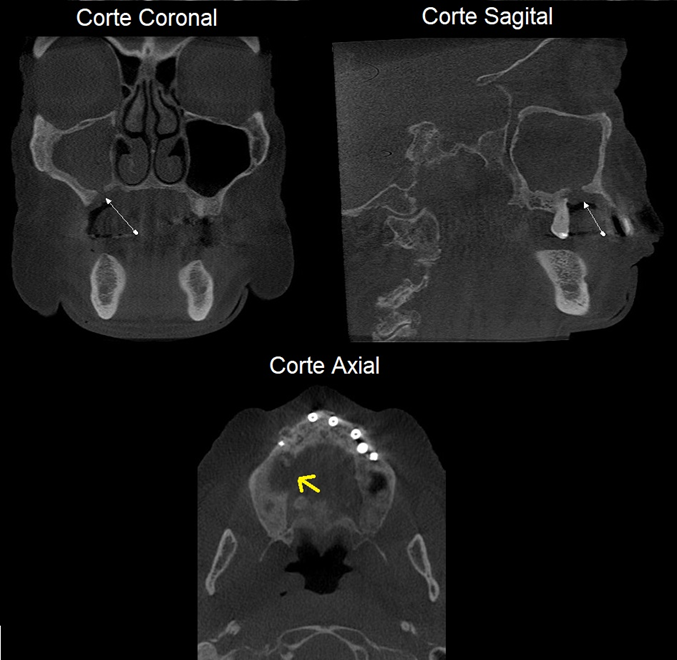

A ONM apresenta maior incidência na mandíbula em comparação com a maxila em uma proporção de 2:1, em áreas com mucosa menos espessa, como as de proeminências ósseas, tórus e linha milo-hioidea. A quantidade de osso exposta é muito variável em suas dimensões. Inicia-se com uma exposição pontual que pode permanecer ou progredir para uma exposição maior. Radiograficamente, é possível observar espessamento da lâmina dura e aumento do ligamento periodontal no osso alveolar no ponto de início da ONM (Figura 1).

As características radiográficas são de áreas de lise óssea de limites irregulares, acompanhadas, por vezes, de reação periosteal das corticais adjacentes. É imprescindível que as informações como a histórico da doença e o uso de medicações sejam relatadas ao radiologista, quando da solicitação do exame.

Algumas vezes pacientes com dor referida em áreas de dentes com tratamentos endodônticos relatam dores e essas podem ter como hipóteses de diagnósticos (HDs) fraturas, trincas, ou canais acessórios também. A Tomografia Cone Beam, nestes casos pode ser um exame decisivo para descartar essas HDs.

Importante ressaltar que A Tomografia Cone Beam pode auxiliar no diagnóstico, mas é fundamental que as informações fornecidas pelo paciente durante a anamnese sejam sempre repassadas ao radiologista na solicitação de forma clara (o que nem sempre ocorre) lhe dando parâmetros para nortear o estudo tomográfico, completa o Dr. Rocha.